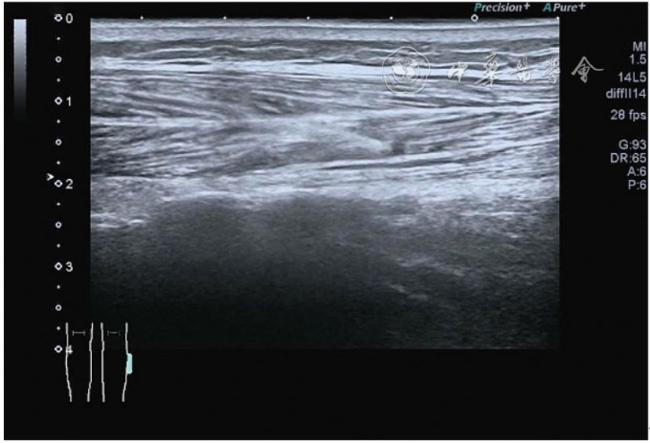

2.膝关节静态结构治疗。动力平衡失调后,继发静态结构变化,出现内外侧副韧带、交叉韧带、脂肪垫、半月板等结构变化。这里介绍半月板与交叉韧带的处理。(1)膝关节静态结构半月板治疗。在膝关节骨关节炎中主要是突出和损伤。突出主要发生于膝内翻引起的内侧半月板突出,引起内侧副韧带的张力增高。内侧半月板与内侧副韧带相连,是引起膝关节内侧疼痛的主要原因之一。治疗主要是针刀剥离松解,部分损伤可行PRP注射。①半月板突出针刀剥离松解治疗。针刀治疗主要是松解和减压,缓解疼痛,不能复位。以内侧半月板突出治疗为例。患者平卧位,髋轻度外展外旋,膝关节屈曲30°,膝下垫一软枕。选用10 MHz超声探头,穿刺区域常规消毒,探头涂抹耦合剂后套入无菌手套碘伏消毒或使用无菌耦合剂。将探头置于患者皮肤表面,内侧关节间隙长轴扫查,找到半月板突出最高点,用25G针头,抽吸1%利多卡因3 ml逐层麻醉直到半月板。选用直径1 mm的Ⅰ型2号针刀从头侧向足侧方向在内侧副韧带与半月板之间,以及半月板内部进行剥离松解3~5刀拔出针刀(图13),局部压迫5分钟,无菌敷料覆盖。②半月板损伤PRP注射治疗。半月板损伤主要表现为髌下痛,伸膝加重,查体在髌下髌韧带与侧副韧带之间,沿关节间隙有固定或局限性压痛,伸膝过程中尤为明显。MRI可示半月板断裂、损伤。如果出现绞索,严重影响功能需手术治疗。半月板损伤治疗,以注射PRP修复为主。以内侧半月板后角损伤为例。患者俯卧位,治疗前准备同半月板突出针刀剥离松解治疗。选用25G注射针头,抽取1%利多卡因2 ml局部麻醉后,制取1.5 ml PRP,穿刺到达半月板撕裂处注射,注射完毕后出针(图14),局部压迫2分钟,无菌敷料覆盖。(2)膝关节静态结构交叉韧带治疗。膝关节骨关节炎交叉韧带损伤多为部分损伤,治疗早期主要为药物或PRP注射,效果不佳时针刀做止点松解。①后交叉韧带损伤药物注射治疗。主要治疗韧带肿胀、无明显断裂患者。患者俯卧位,膝关节伸直位。一般选用10 MHz超声探头,治疗前准备同半月板突出针刀剥离松解治疗。将探头置于患者皮肤表面,后交叉韧带长轴扫查,找到胫骨止点,选用22G长针头,抽吸1%利多卡因3 ml+曲安奈德10 mg,从头侧向足侧方向穿刺到后交叉韧带胫骨止点部位的韧带表面进行注射,注射结束拔出针头(图15),局部压迫2分钟,无菌敷料覆盖。②前交叉韧带损伤PRP注射治疗。患者仰卧位,膝关节伸直。选用10 MHz超声探头,治疗前准备同半月板突出针刀剥离松解治疗。将探头置于患者皮肤表面,短轴扫查,找到前交叉韧带胫骨止点,选用25G针头,抽吸1%利多卡因3 ml逐层麻醉直到韧带止点部位,制备PRP 3 ml注射到前交叉韧带显露部位,注射结束拔出针头(图16),局部压迫2分钟,无菌敷料覆盖。③前交叉韧带损伤针刀剥离松解治疗。体位与治疗前准备同前交叉韧带损伤PRP注射治疗。短轴扫查找到前交叉韧带胫骨止点,选用25G针头,抽吸1%利多卡因3 ml逐层麻醉直到韧带止点部位,选用直径0.6 mm的Ⅰ型2号针刀从外侧向内侧于前交叉韧带胫骨止点部位剥离松解3~5刀拔出针刀(图17),局部压迫5分钟,无菌敷料覆盖。

图13 超声引导下半月板突出针刀剥离松解治疗